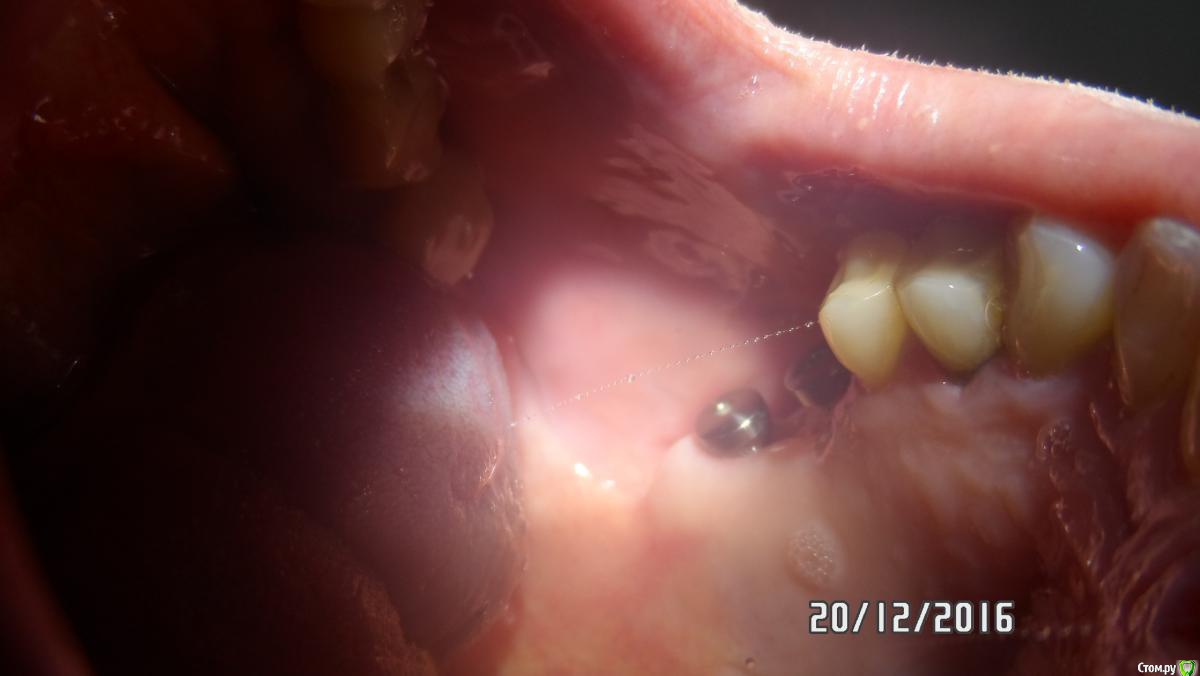

Sergiosse Опубликовано 21 декабря, 2016 Поделиться Опубликовано 21 декабря, 2016 Меньше 2 месяцев назад были установлены два импланта диаметром 4,2х12и10 в области 16 17 зубов одномоментно с удалением. Скриншоты выкладывал в теме: оголился имплант. Сейчас посоветовавшись с вами Уважаемые форумчане пришел к выводу о необходимости переустановить имплантанты . С какими особенностями могу столкнуться. Кто делал подобные манипуляции, пожалуйста подскажите. Заранее спасибо всем ответившим.Р.С. Недавно один уважаем доктор сказал, что, я не настоящий имплантолог. Стану им только тогда, когда удалю собственноручно установленный имплант. Чувствую скоро, я стану настоящим Ссылка на комментарий